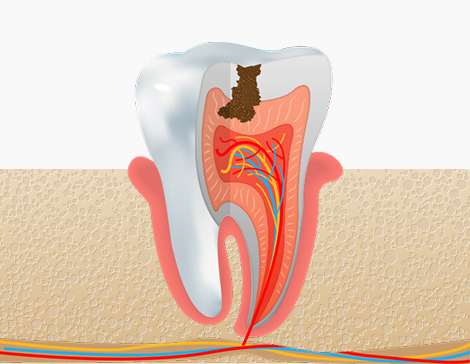

충치치료,

손상 정도에 따라 달라지는 맞춤 진료

충치 부위를 제거하고 치아색 재료로 메워 원래 모양과 기능을 복원합니다.

초기에 치료하면 간단하지만, 방치 시 신경치료까지 이어질 수 있습니다.

충치의 단계의 증상

충치 1단계

법랑질(치아의 가장 바깥층)

치료방법

레진치료 : 충치 부위를 제거하고 치아색 재료로 메움

충치 2단계

상아질 경계 또는 상아질층까지

인레이 / 온레이 치료 : 손상된 부위만 제거 후 부분 보철로 복원

충치 3단계

치수(신경)까지 진행

신경치료 후 크라운 보철 : 감염된 신경 제거 후 치아 전체 보강

충치 4단계

치근, 치조골·잇몸까지 진행

발치 및 임플란트 / 브릿지 : 염증 부위 제거 후 대체치료 진행